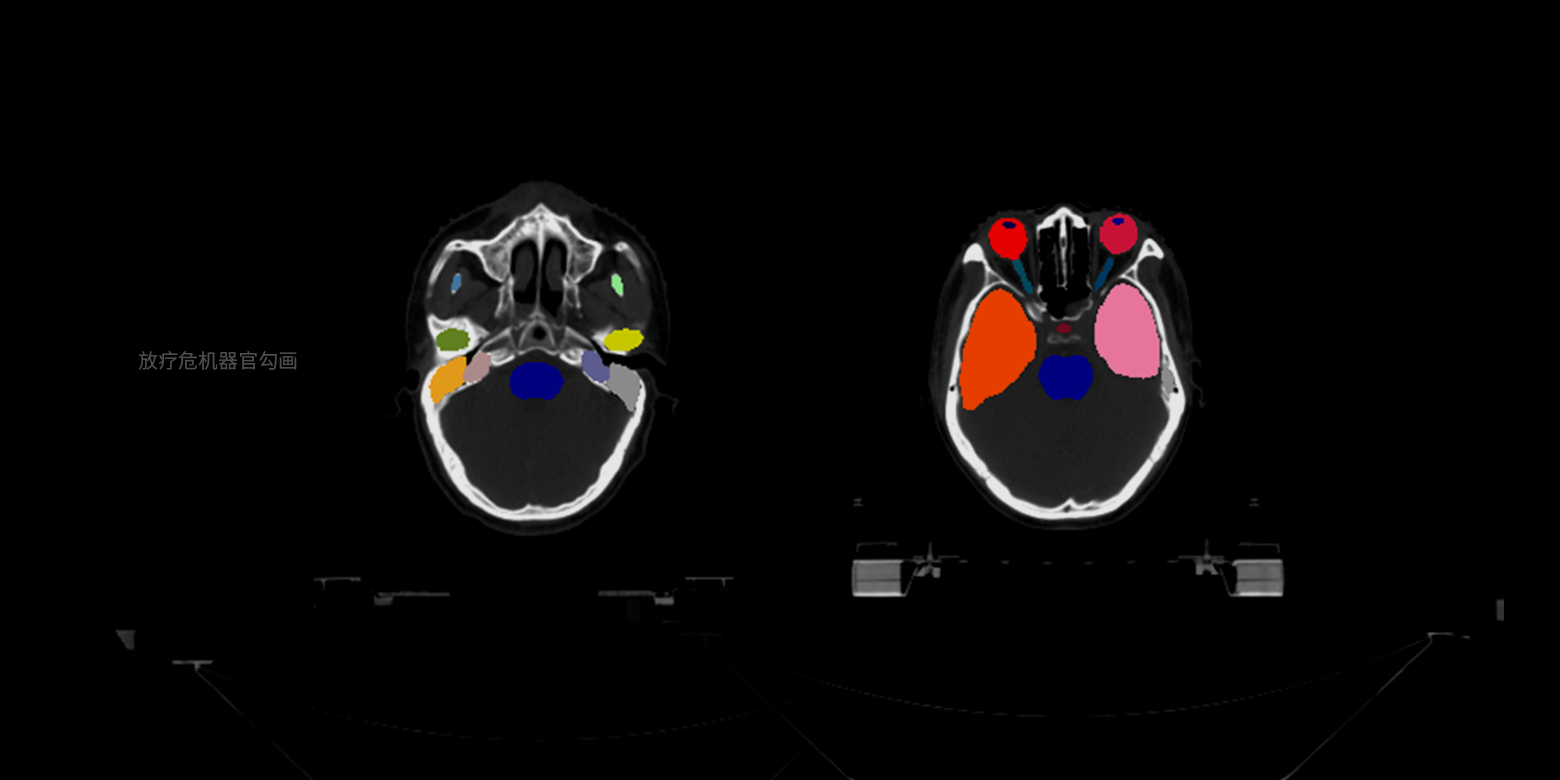

病灶/部位分割与量化

支持基于小样本精细医学数据标注进行训练,实现多种病灶、器官等的像素级精确边界分割,并自动进行关键信息的量化分析,例如放疗靶区勾画、骨盆肿瘤分割等,将医生从耗时耗力的人工手动勾画中解放,满足量化诊断、手术个性化规划等场景的需求。

病灶/部位分割与量化

支持基于小样本精细医学数据标注进行训练,实现多种病灶、器官等的像素级精确边界分割,并自动进行关键信息的量化分析,例如放疗靶区勾画、骨盆肿瘤分割等,将医生从耗时耗力的人工手动勾画中解放,满足量化诊断、手术个性化规划等场景的需求。